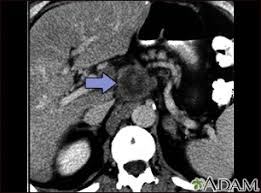

A ct scan can show possible concerning findings based on a radiologist's interpretation of what is seen. This ct scan of the upper abdomen. Digital breast tomosynthesis (dbt) was introduced in 2011 and approved by the fda for breast cancer screening and diagnosis. Ct scans are most often an outpatient procedure. Understanding pathology for breast cancer.

The results of these tests can give your doctors a. In some cases, physicians use all three imaging techniques. What can a ct scan show that an mri cannot? A ct scan can show possible concerning findings based on a radiologist's interpretation of what is seen. A ct scan can show whether breast cancer has spread to the lungs or liver. Ct scans can show a tumor's shape, size, and location. A radiographer operates the scanner. Digital breast tomosynthesis (dbt) was introduced in 2011 and approved by the fda for breast cancer screening and diagnosis. Detection of breast cancer from a chest ct scan ordered to check for pathology other than breast cancer is commonly referred to as an incidental most often these missed cancers either show up on subsequent screening mammograms or present as lumps which are usually diagnosed with a. For example, it could be scar tissue left over from cancer killed off by. For patients showing up in the emergency. At the low doses of radiation a ct scan uses, your risk of developing cancer from. A computed tomography (ct or cat) scan allows doctors to see inside your body.

Ct scans can show a tumor's shape, size, and location. A ct scan of the middle abdomen showing a large tumor mass due to metastasis (spreading cancer) in abdominal lymph nodes. A ct scan may be used to look for tumors in organs outside of the breast, such as the lung, liver, bone, and lymph nodes. A computed tomography (ct or cat) scan allows doctors to see inside your body. Diagnose and assess breast tumors.